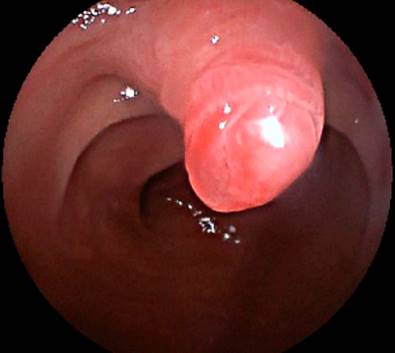

Se ingresa por el asa biliopancreática (con ayuda de la fluoroscopia) hasta el muñón duodenal (aproximadamente 150 centímetros de longitud) (Figura 3). Se identifica la papila duodenal de aspecto normal (en el cuadrante superior) (Figura 4). Se intenta la canulación con catéter punta cónica, con papilótomo de arco y con papilótomo de aguja, pero no es posible avanzar la guía hacia la vía biliar, por lo que se utiliza un papilótomo invertido; se logra avanzar la guía hidrofílica hacia la vía biliar (Figura 5).